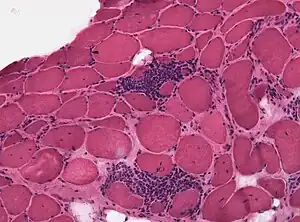

| Congenital nemaline myopathy (neuromuscular disorder) | |